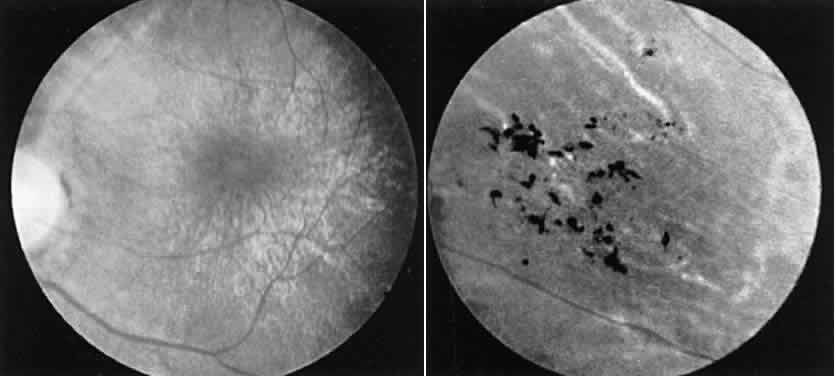

The physician who deals with a hereditary problem becomes the first line in genetic counseling. Making the correct diagnosis is the initial step, but it is likewise important to ascertain, as far as possible, the hereditary mode of the disease. In the case of retinitis pigmentosa, where all three modes of inheritance are seen, the importance becomes obvious with regard to future generations. If an individual is seen without a positive family history, autosomal recessive is statistically the most likely mode of inheritance.11 But if one further considers an isolated case of a male presenting with such a problem, the possible diagnosis of X-linked recessive retinitis pigmentosa cannot be ruled out. In such a case it is important to examine any female who might be the carrier of the X-linked gene. In a large percentage of such cases the female carrier shows fundus changes in the absence of any subjective complaints.12 These may consist of an unusual scintillating reflex in the macular area or a clumping of pigment in the periphery (Fig. 13). However, these changes are not always seen. In such cases electrophysiologic studies provide the answer, for it has been found that certain electrophysiologic abnormalities also are seen in the majority of female carriers, even those with no fundus abnormalities. These consist of a prolonged photopic b-wave implicit time and/or a reduction in the amplitude of the scotopic b-wave in a fully dark-adapted eye.13

Fig. 13. Female carrier of X-linked retinitis pigmentosa. Fundus photographs of a 48-year-old female with vision of 20/20 OD and OS. Left. Macular area shows an unusual scintillating reflex around the entire parafoveal region. Right. Retinal periphery showing an isolated area of retinal pigment epithelial loss with associated clumps of pigment.